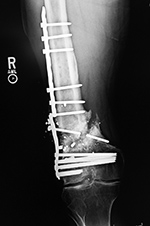

| Right femur periarticular plate breakage and chronic fracture nonunion |

| 36 year-old man with bullet wound in 2003 complicated by femur fracture infected non-union treated by multiple attempts with external fixation and open reduction and internal fixation (ORIF). Radiography 12 years later shows chronic fracture hypertrophic nonunion, multiple shrapnel fragments, and breakage of a periarticular fixation plate. |